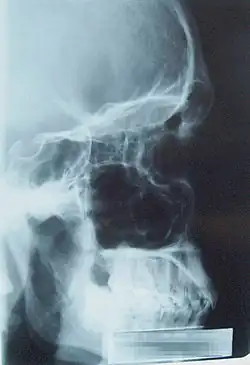

Zobrazovací metody (angl. medical imaging) představují celou škálu metod umožňujících získat pohled do těla nemocného. Patří sem především:

- radiodiagnostika – zejm. skiagrafie, CT a MR